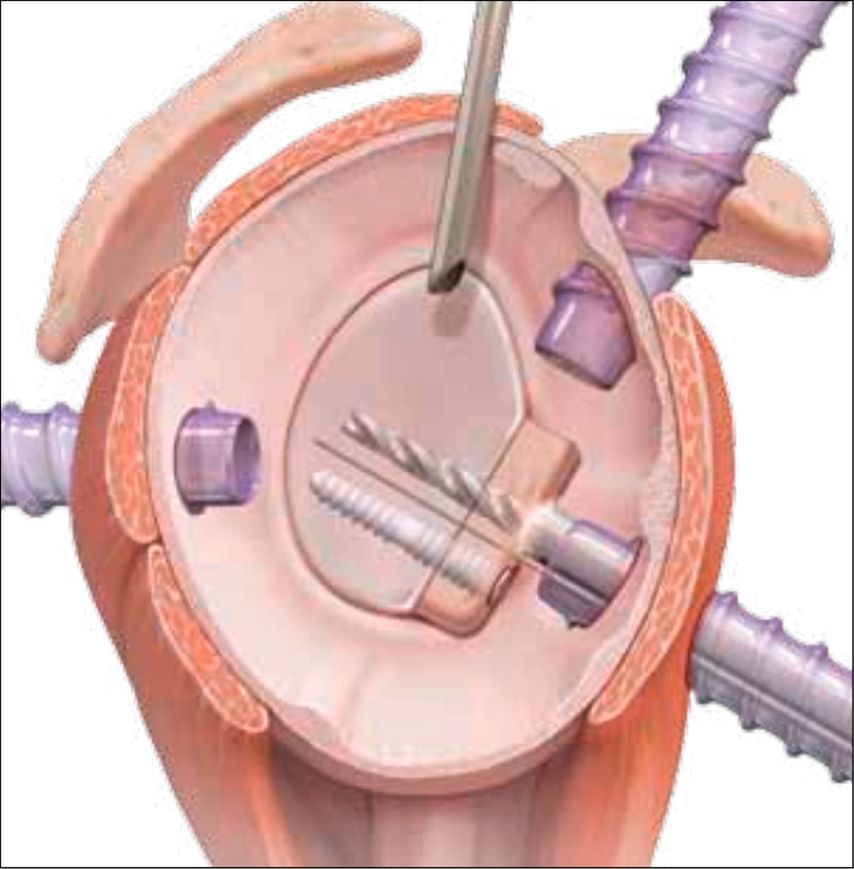

Zur definitiven Fixation stehen unterschiedliche Techniken zur Verfügung. Die arthroskopisch assistierte Schraubenosteosynthese wird meistens durch das 5-Uhr-Portal durchgeführt. Kanülierte Schrauben (2,7–3,5mm) bieten, insbesondere bei größeren, kompakten Fragmenten, eine hohe Primärstabilität, ihr Einsatz ist jedoch technisch anspruchsvoll und mit dem Risiko einer intraartikulären Implantatprominenz verbunden. In den letzten Jahren sind aber Systeme mit bioresorbierbaren Implantaten hinzugekommen, die für die vordere Glenoidaugmentation entwickelt wurden (Abb. 5). Dieses System eignet sich auch perfekt für die Fixation des Glenoidfragments.